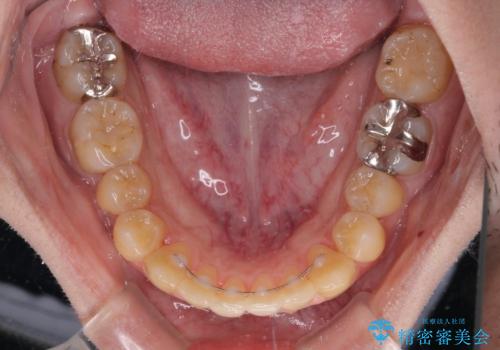

前歯のクロスバイトをインビザラインで矯正治療

- 前歯のデコボコとクロスバイトを気にして来院された患者様です。

前歯を早く整えたいとの希望があったので、ワイヤー矯正にて短期間でクロスバイトを解消し、その後インビザラインにて整えることとしました。

インビザラインによる前歯のクロスバイト改善におけるリスクとして、前歯歯髄充血・歯髄壊死が挙げられます。

ワイヤー矯正を併用する目的として、短期間でデコボコやクロスバイトを改善する他に、歯髄充血リスクを低減させるというものがあります。